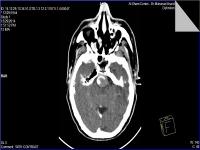

Medical imaging is an important investigative tool will help doctors to reach for the diagnosis of certain diseases, and the the advanced and high-quality imaging technologies are an important factor in maintaining the health of patients and accurate diagnosis of pathological lesions.